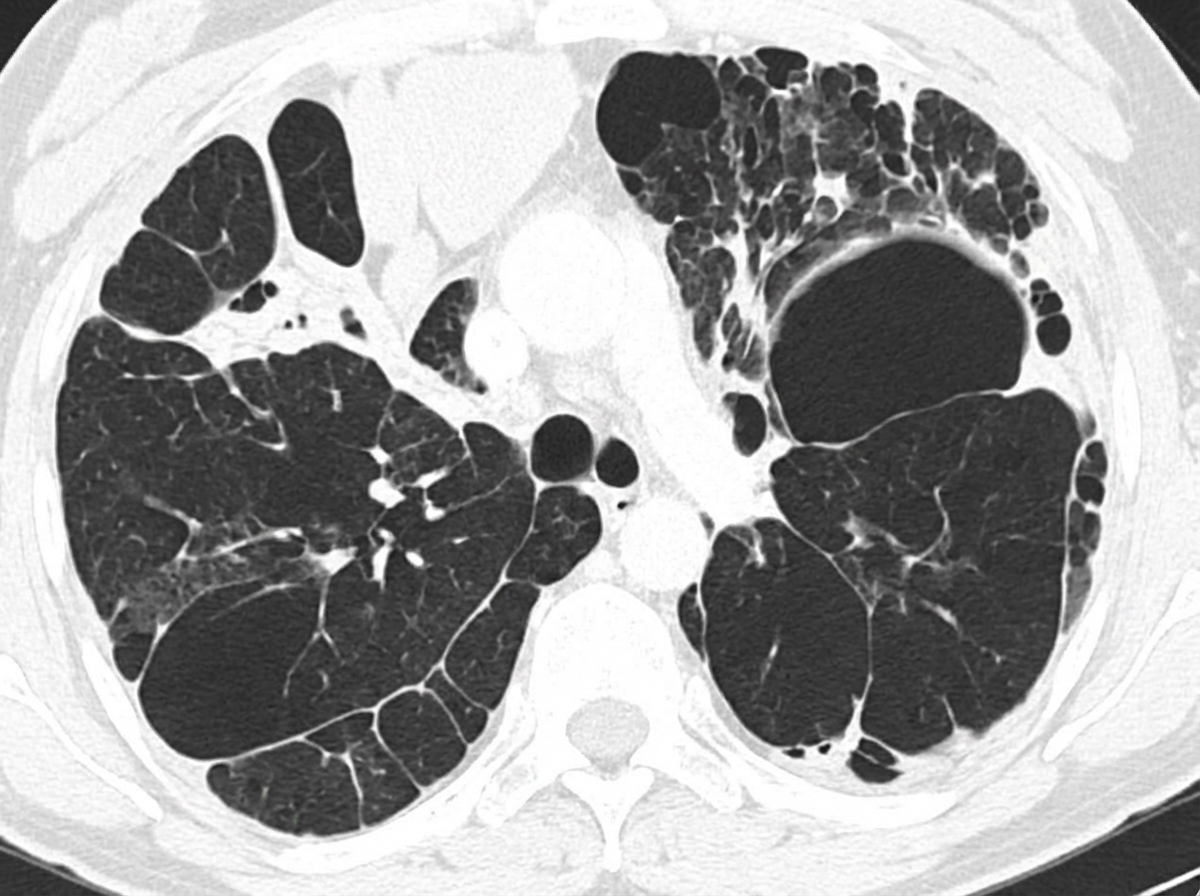

A 58-year-old woman presents to the physician with a cough that began 6 years ago, as well as intermittent difficulty in breathing for the last year. There is no significant sputum production. There is no history of rhinorrhea, sneezing or nose congestion. She has been a chronic smoker from early adulthood. Her temperature is 36.9°C (98.4°F), the heart rate is 80/min, the blood pressure is 128/84 mm Hg, and the respiratory rate is 22/min. A physical examination reveals diffuse end-expiratory wheezing with prolonged expiration on chest auscultation; breath sounds and heart sounds are diminished. There is no cyanosis, clubbing or lymphadenopathy. Her chest radiogram shows hyperinflated lungs bilaterally and a computed tomography scan of her chest is shown in the picture. Which of the following best describes the pathogenesis of the condition of this patient?